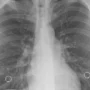

JABAR EKSPRES – Di tengah pertanyaan banyak orang tentang perbedaan antara pneumonia biasa dan infeksi akibat bakteri mycoplasma, Jakarta menghadapi...

JABAR EKSPRES – Flu dan pneumonia pada anak keduanya adalah penyakit yang menyerang saluran pernapasan dan dapat menyebabkan gejala yang...

JAKARTA – Ketua Kelompok Kerja (Pokja) Infeksi, Perhimpunan Dokter Paru Indonesia (PDPI), dokter Erlina Burhan mengatakan pemberian vaksin pneumonia menjadi...